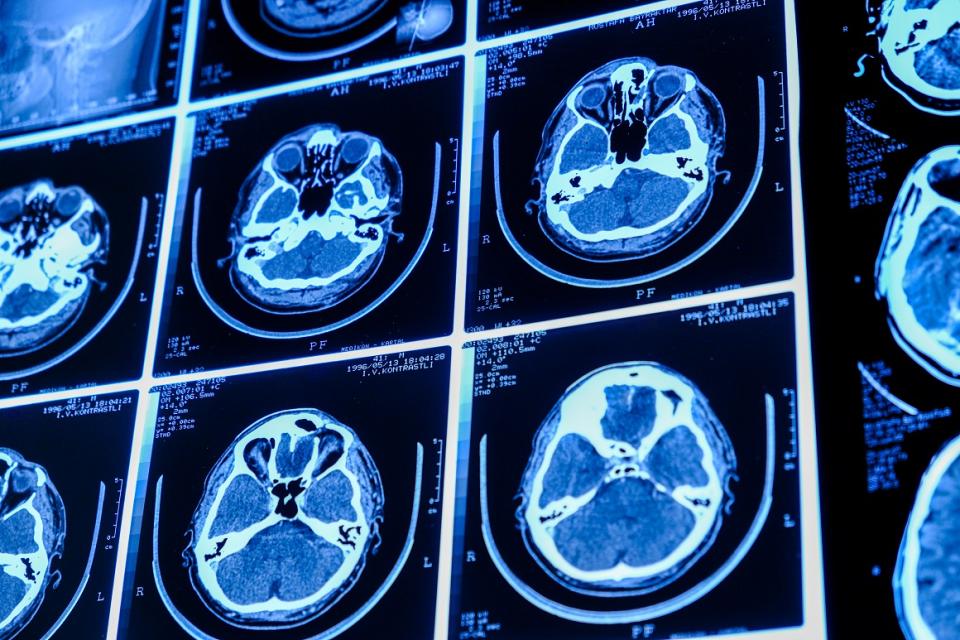

Le service de neuroradiologie interventionnelle de l’hôpital de Jolimont : expertise et innovation au service des patients.

À l’hôpital de Jolimont, une équipe spécialisée prend en charge les pathologies neurovasculaires de manière mini-invasive, avec des techniques de pointe.

• Les anévrismes cérébraux

• Les malformations artério-veineuses

• Les hématomes sous-duraux chroniques